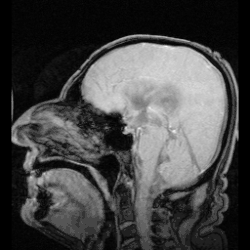

![]() The cerebrospinal fluid circulates in the subarachnoid space around the brain and spinal cord, and in the ventricles of the brain. | |